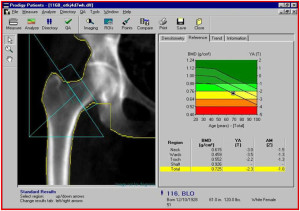

Важно понимать, что в результате такого анализа проводится измерение не самой минеральной плотности костной ткани. Оцениваются Z и Т-критерии. То есть существуют определенные нормы, отклонение от которых считается определенной стадией остеопороза.

Под Т-критерием понимается количество стандартных отклонений ниже и выше среднего показателя массы костей у молодых женщин в возрастной категории от 30 до 35 лет. Когда увеличивается возраст, в норме снижается и костная масса, поэтому критерий тоже уменьшается.

Под Z-критерием понимается число стандартных отклонений, находящихся ниже или выше среднего показателя, но уже у пациентов средневозрастной нормы. Этот критерий позволяет учитывать даже снижение костной плотности в пределах нормы, которое происходит с возрастом.

Отсутствие или наличие остеопороза, как и степень его выраженности, определяются по Т-критерию. Оценку минеральной плотности костной ткани советуется проводить один раз в год, особенно при наличии факторов риска.

Если рассматривать возможные показатели анализов, то есть те, которые находятся в пределах нормы и те, которые говорят о наличии заболеваний. Хорошие показатели – не больше -1 стандартного отклонения от костной пиковой массы по Т-критерию. Если развивается остеопения, в зависимости от ее степени результаты будет не более -2,5. При остеопорозе показатели больше той цифры.